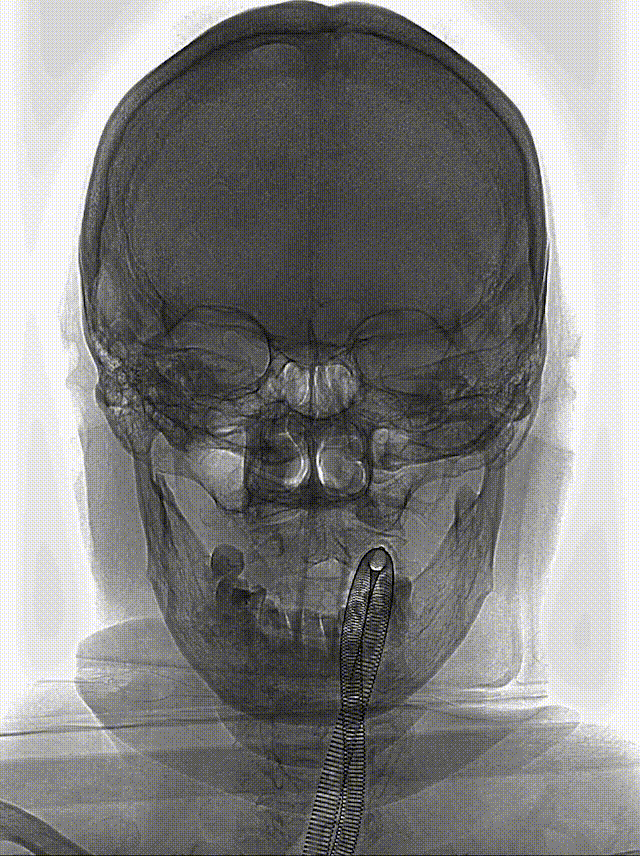

React™ 68远端通路导管内路图证实左侧C7段闭塞,支架到位后释放。

支架释放后造影:

术后24h CT:

左侧外囊区梗死